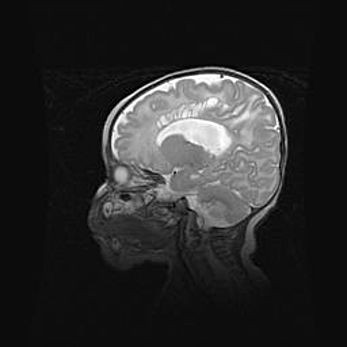

Лейкомаляция с кистозно-глиозной дегенерацией головного мозга.

Возраст: 2 месяца 25 дней

Вес: 6400 г

Окружность головы: 40 см

Срок гестации: 41 неделя

Лейкомаляцию относят к ишемически-гипоксическим повреждениям головного мозга, диагностируемым у новорожденных. При лейкомаляции в головном мозге обнаруживают очаги некроза, возникшие после тяжелой гипоксии и нарушения кровотока. В процессе морфогенеза очаги проходят три стадии: 1) развития некроза, 2) резорбции и 3) формирования глиозного рубца или кисты. Перивентрикулярная лейкомаляция (ПЛ) встречается примерно в 12% случаев среди новорожденных, обычно – у недоношенных детей, причем, частота ее зависит от массы, с которой младенец появился на свет. Наибольшее число малышей страдает лейкомаляцией, если масса при рождении 1500-2500 г.